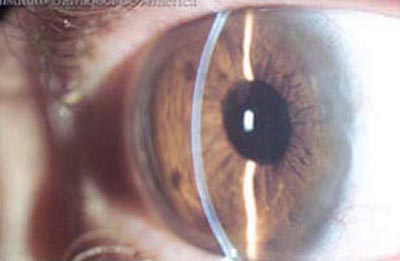

Ojo Sano

Ojo Sano, Foto tomada en Lampara de Hendidura

Segmentos Intracorneales: (Anillos): Los segmentos intracorneales son segmentos de acrílico de forma semicircular que se insertan dentro de la córnea en su perifería para dar soporte, regularizar y aplanar la superficie anterior deformada por la ectasia; como efecto secundario corrigen parcialmente la miopía y el astigmatismo inducidos por la deformación. Se insertan a través de un incisión pequeña que se realiza con un laser Femtosegundo o en forma manual, con instrumentos especialmente diseñados para ello; La previsibilidad del resultado refractivo es relativa. Hoy en día se emplean para aplazar la intervención del transplante de córnea.